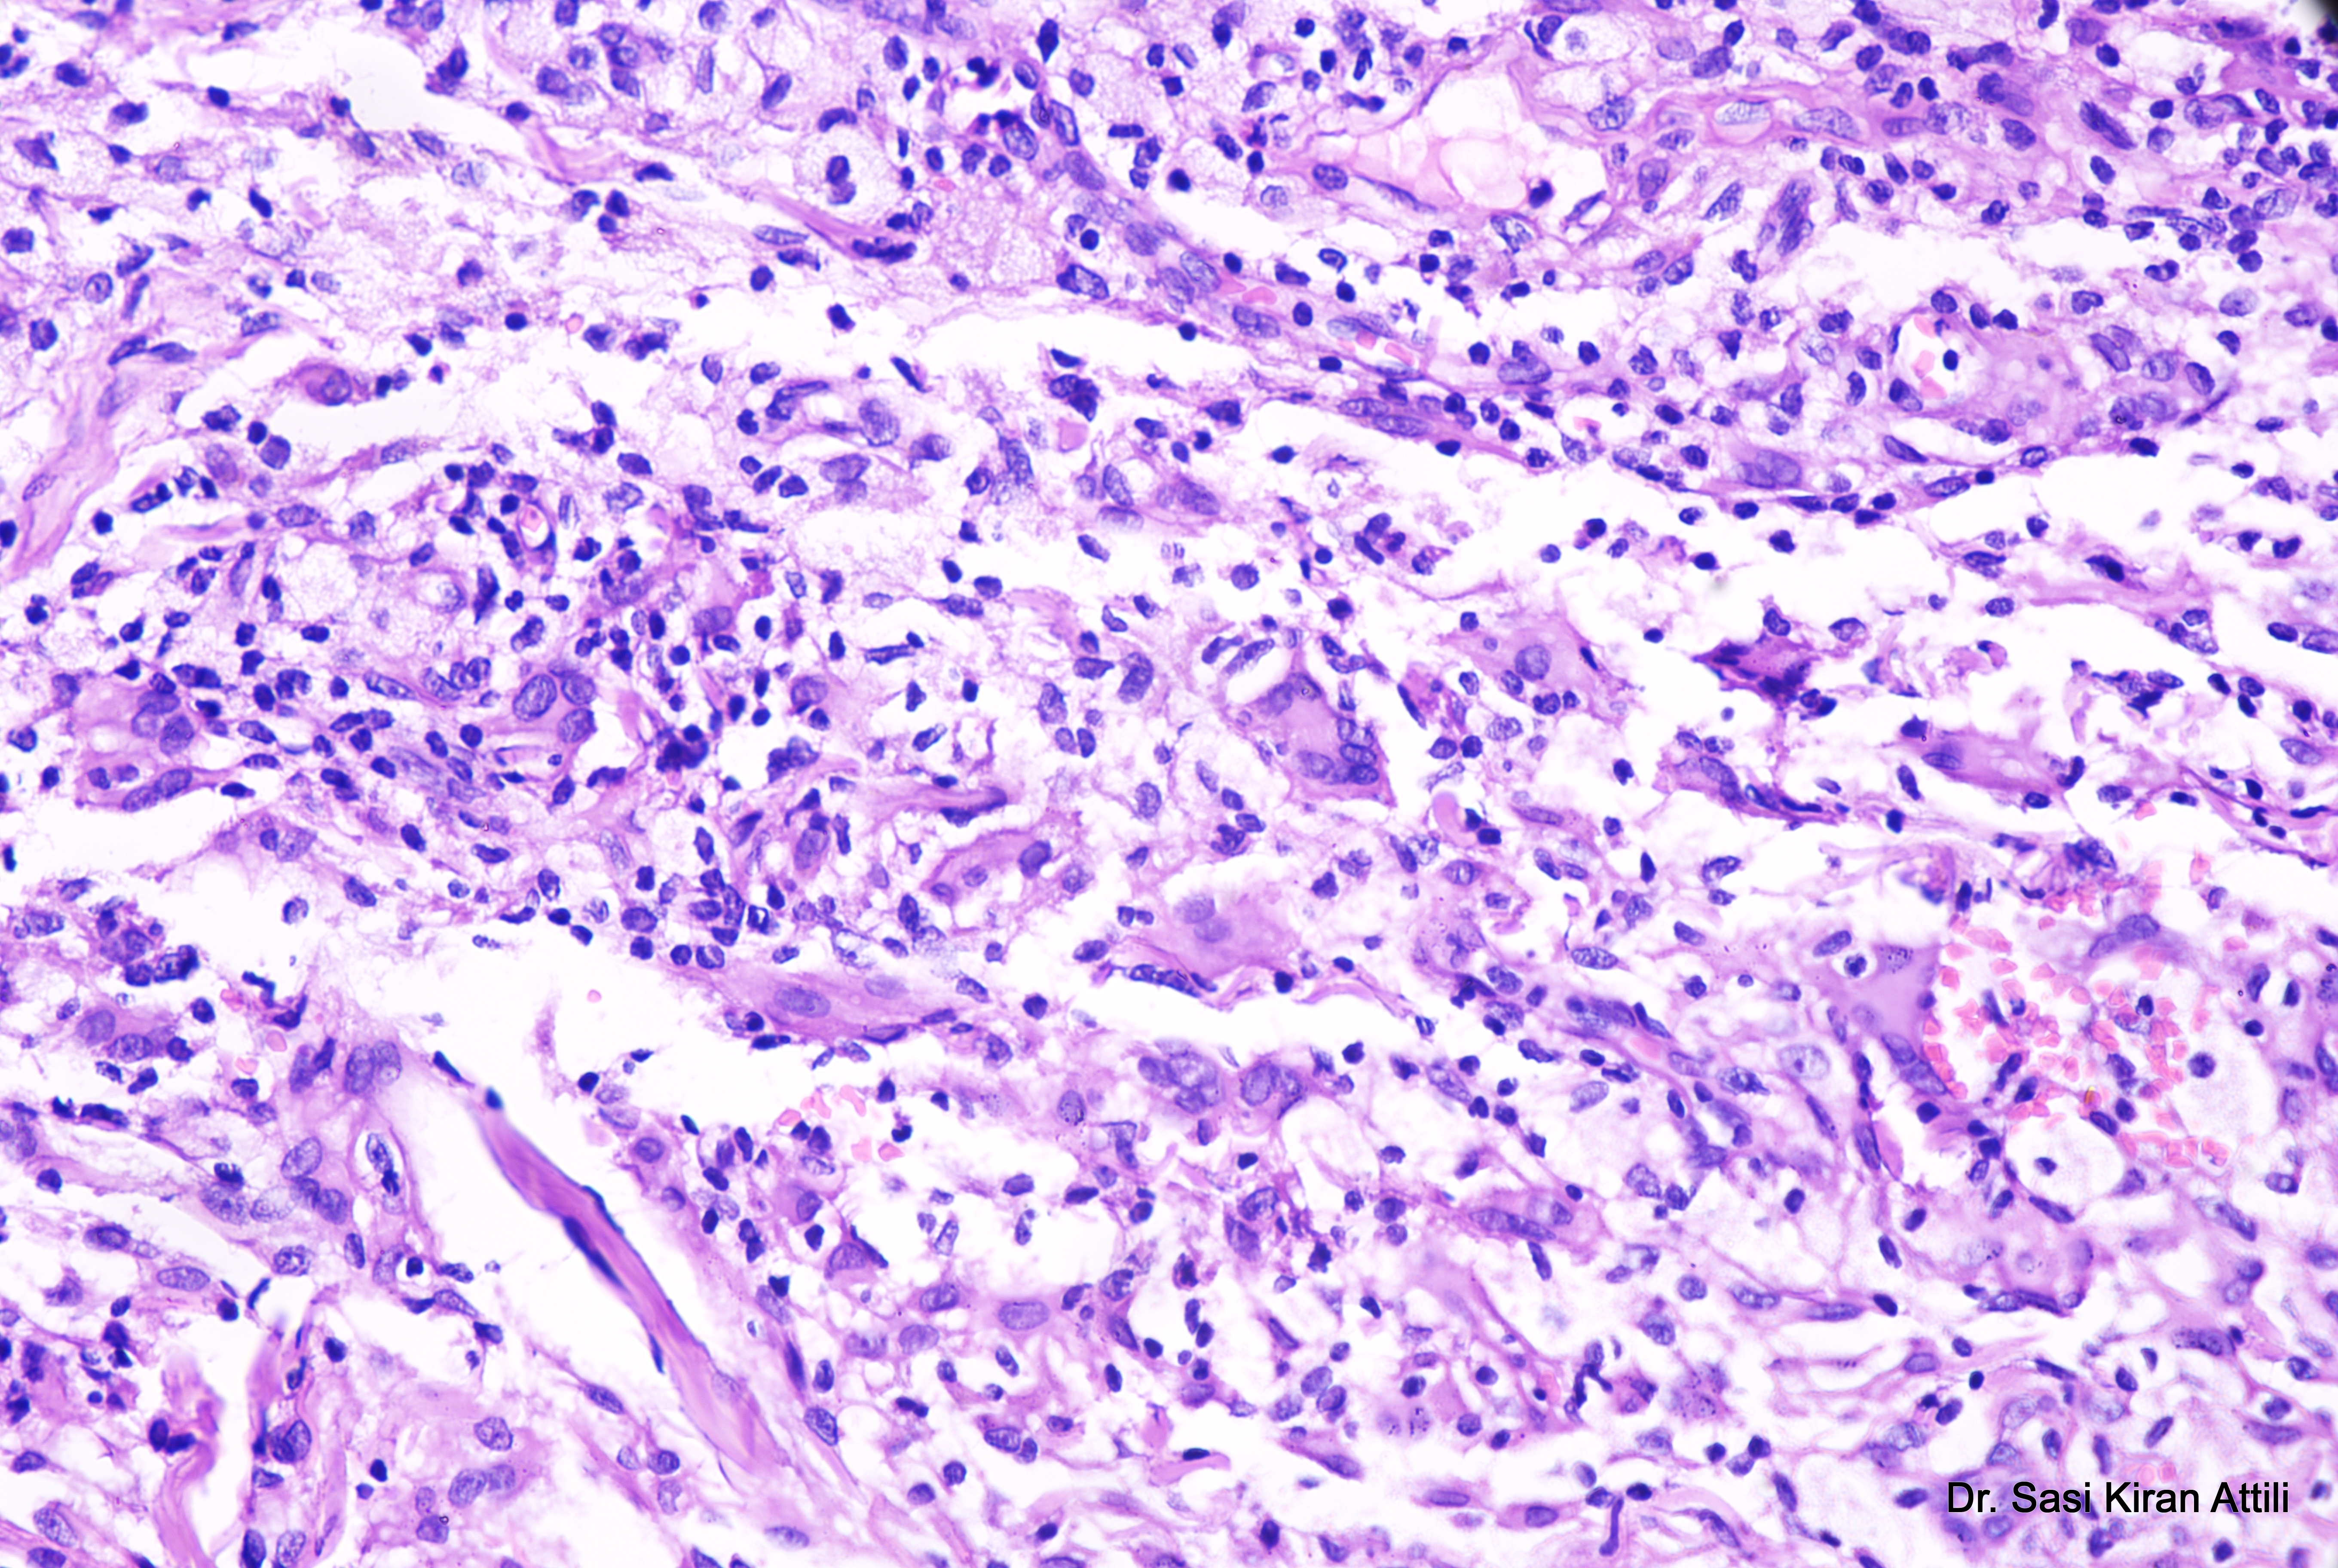

A 21-year-old male presented with a 2-year history of multiple brownish skin lesions over the face, neck, both axillae, both upper limbs, both popliteal fossae, and both flanks, with aggregation on the flanks over the last 4 months. Examination revealed multiple confluent necrotic macules and papules over the face, auricular area, axillae, inguinal regions, knees, and flanks, with ill-defined yellowish macules on the upper and lower lips and buccal mucosae. Genital mucosa was normal. Cerebral